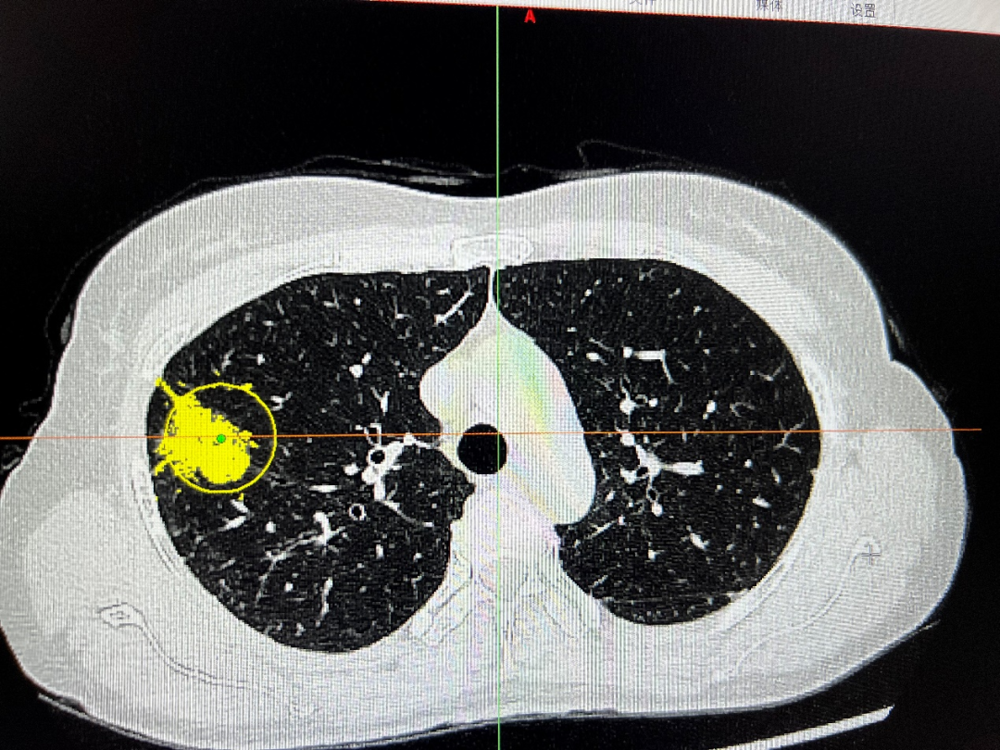

病例一: 雙側肺(fèi)癌(ái)同時(shí)手術病例患者,黎xx,女,55歲,發現肺部陰影(yǐng)2周(zhōu)入院。查體:生命體征平穩,心肺無(wú)明顯異常。輔助檢查:我院頭顱全腹部及(jí)胸部增強CT示:1、右肺上葉部分實性腫塊並兩肺多發部分實性、實性及磨玻璃結節,增強呈輕支中度強化,考(kǎo)慮右肺上葉肺Ca並肺內多(duō)發轉移可能,不排外非特異性感染(rǎn)或其他病變,建議纖維支氣管鏡及活檢(jiǎn)或穿刺檢查;兩肺少許纖維條索灶。2、顱腦、腹(fù)部、盆腔CT平掃未見明顯異常。診斷為雙肺多發性肺癌入院。患者有肺(fèi)結核病史,主病(bìng)灶在右肺上葉,次病灶在左肺下葉背段,為複雜手術。左側(cè)病(bìng)灶考慮原發性肺癌。術前與影(yǐng)像科及(jí)其麻醉科反複交流,患者身體條件尚(shàng)可,肺功能正常。術前決(jué)定行單孔胸腔(qiāng)鏡下雙側肺癌手術(shù)(胸腔鏡下(xià)右肺上葉切(qiē)除+左下肺背(bèi)段切除+雙側縱膈淋巴清掃)。術(shù)中在(zài)麻醉科周迎(yíng)春主任及蘭丙豐(fēng)醫師(shī)的大力支持下,保(bǎo)證患者在雙側(cè)手術過程中,生命體征穩定。術後安全(quán)返回病房,患者無(wú)疼痛等不適(術中打了肋間神經阻滯)。武寧縣人民醫院胸外科正式進入肺段切(qiē)除(chú)時代。

術前胸部CT

術中腫瘤位置